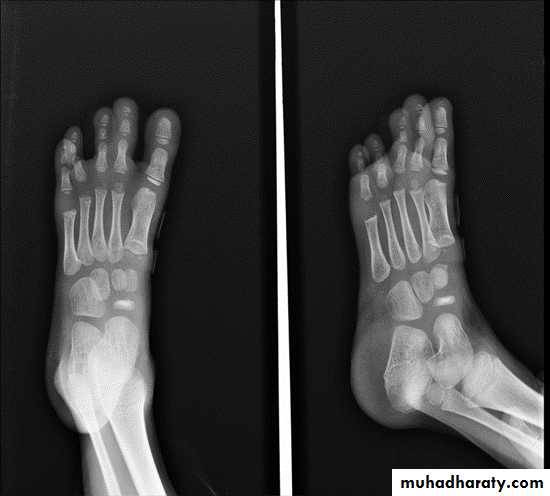

GOUT

Heterogeneous group of entities characterized by recurrent attacks of arthritis secondary to deposition of sodium urate crystals in and around joints.

Radiographic features:

Lower extremity > upper extremity; small joints > large joints

* First MTP is most common site

* Marginal, peri articular erosions: overhanging edge

* Erosions may have sclerotic borders

* Joint space is preserved

* Soft tissue and bursa deposition

Tophi: juxtaarticular, helix of ear

* Tophi calcification, 50%

*Chondrocalcinosis